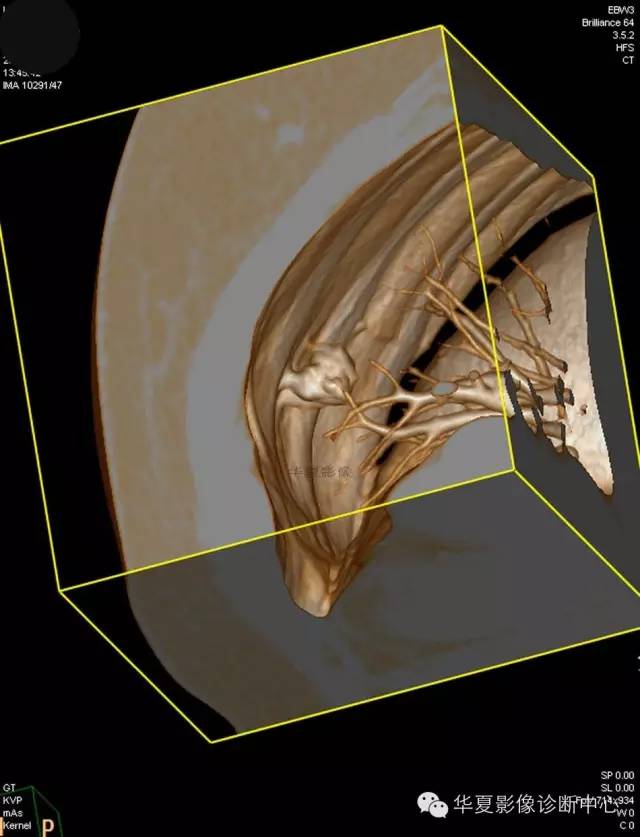

【病例学习】典型周围型肺癌CT病例一例

女,56岁,其父因肺癌去世,自觉胸部疼痛不适来诊要求拍胸片。

1.右肺上叶:肺组织1块,大小13×4×7cm。切面棕红色。2.右肺上叶肿物:灰白色组织一块,大小3×1×1.5cm。切面灰白色。3.右肺中叶结节:灰白色绿豆大组织1块。4.淋巴结:灰黑色绿豆大组织1块。

(右)肺中分化鳞状细胞癌。浸及胸膜。支气管残端切净。淋巴结未见癌转移(0/10)。